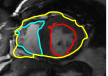

![]() |

| image + boundary | global optical flow | our method | our method (motion decomp.) |